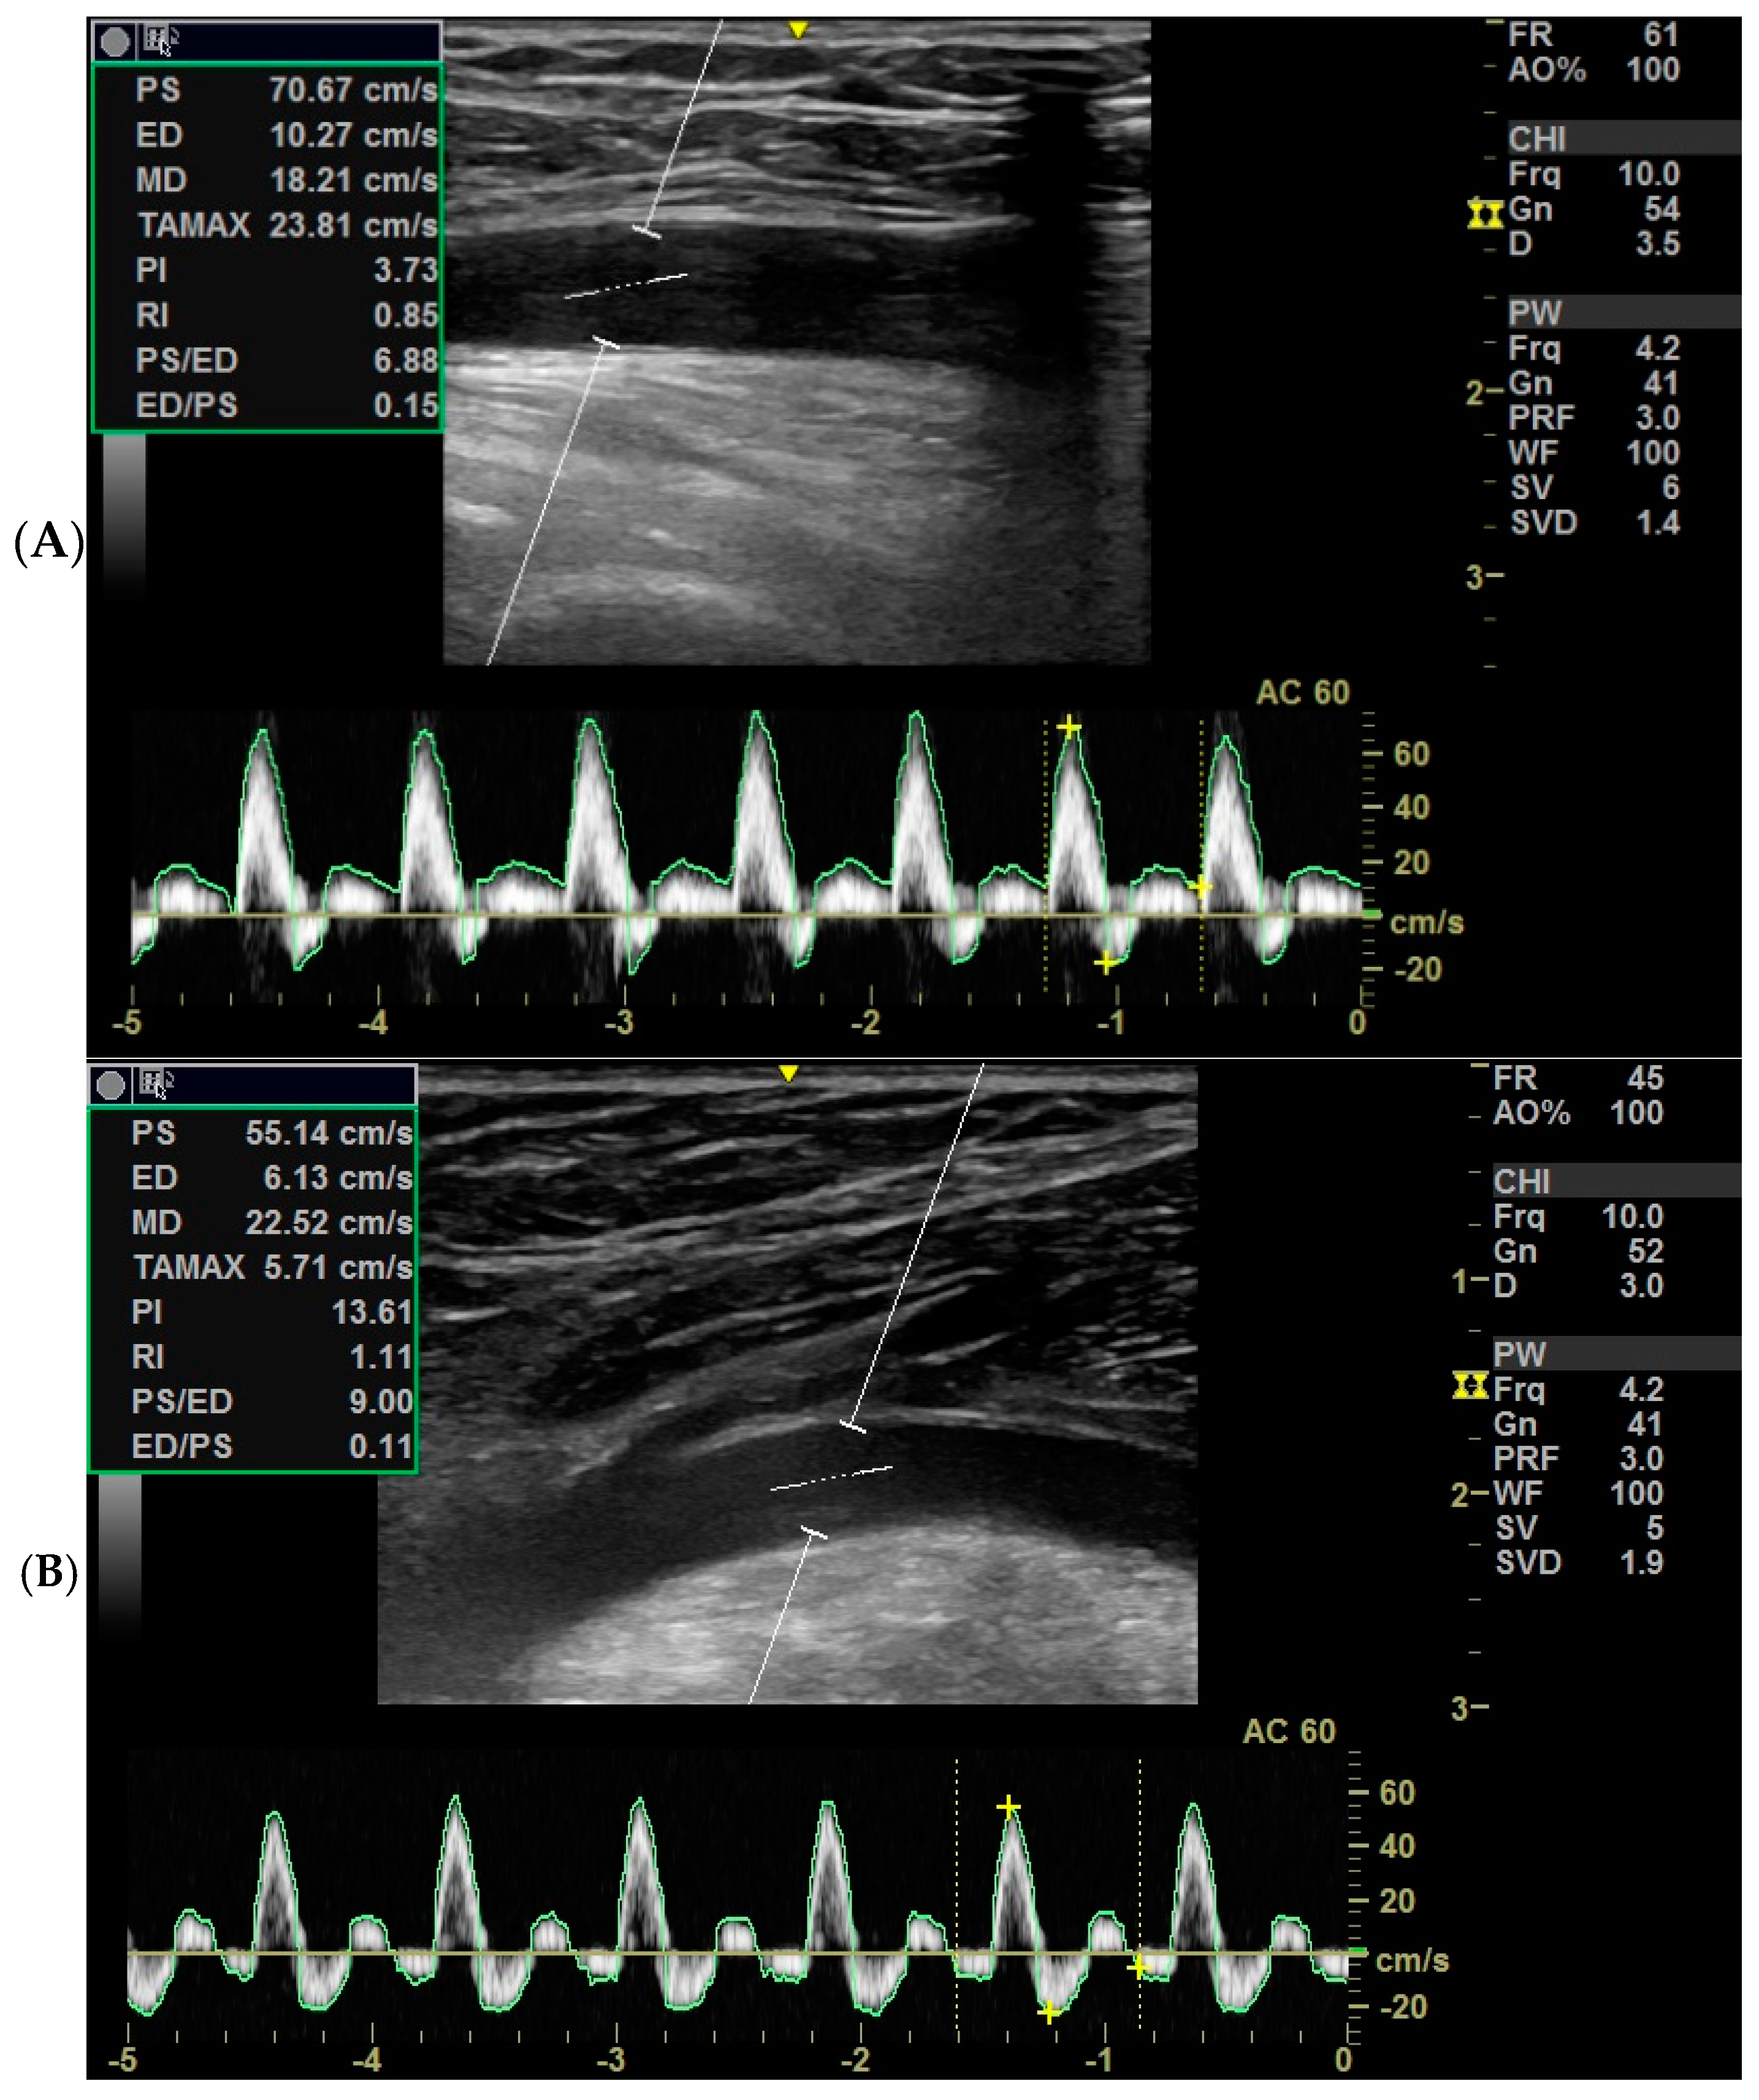

Color Doppler techniques were conducted using the vascular setting of the same ultrasound machine (Next Generation LOGIQ e ultrasound; General Electric, Fairfield, CT, USA). Participants were positioned supine while obtaining short- and long-axis images of the femoral artery in the anterior groin region. For the popliteal artery, participants assumed a prone position with their knees comfortably extended, and the transducer was placed in the popliteal fossa to capture the necessary images. Grayscale pulsed and color Doppler flow imaging were employed during both systolic and diastolic intervals. Cross-sectional areas of the femoral and popliteal arteries were calculated using lumen measurements from transverse images, as per the GE measurement settings (Figure 1A,B). The resistance index, systolic/diastolic ratios, and pulsatility index were computed to evaluate blood flow from the generated waveform [14] (Figure 2).

Doppler ultrasound was performed to assess the popliteal and femoral arteries, recording several hemodynamic parameters. Peak Systolic Velocity (PS, cm/s) represents the maximum blood flow velocity observed during the systolic phase. End-Diastolic Velocity (ED, cm/s) refers to the blood flow velocity at the end of diastole, with cases where ED = 0 excluded from averaging to prevent skewed results. Minimum Absolute Velocity in the Diastolic Cycle (MD, cm/s) represents the lowest recorded velocity during diastole. Time-Averaged Maximum Velocity (TAMAX, cm/s) is the maximum velocity averaged across multiple cardiac cycles, assessing peak flow dynamics. Cross-Sectional Area (CS, mm2) was estimated based on arterial diameter using the equation CS = π × (MD/2)2, providing an estimate of vessel luminal area and reflecting potential structural or functional changes [15]. Each parameter was measured three times, with the average used for analysis to ensure reliability [15].

The following Doppler indices were derived from the measured parameters. Pulsatility Index (PI) was calculated as PI = (PS − ED)/MD, reflecting blood flow pulsatility and arterial compliance. Resistive Index (RI) was computed as RI = (PS − ED)/PS to assess downstream vascular resistance. Systolic/Diastolic Ratio (PS/ED) was determined using PS/ED = PS/ED, evaluating arterial resistance and compliance. Diastolic/Systolic Ratio (ED/PS) was calculated as ED/PS = ED/PS, serving as an inverse measure of arterial compliance and providing insights into diastolic blood flow relative to systolic peak velocity. These indices were analyzed to assess vascular health and function, with values interpreted in the context of normal hemodynamic responses [15].

Figure 1. Standard Doppler indices of (A) the femoral artery and (B) the popliteal artery.